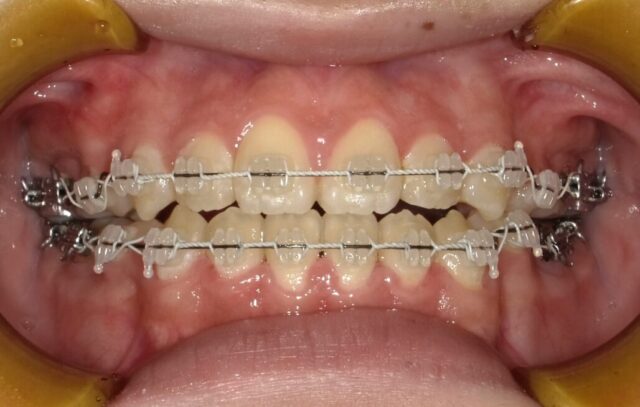

≪正面観≫

2023年5月

2023年6月

2023年7月

2023年8月

2023年9月

2023年10月

2023年11月

2023年12月

2024年1月

2024年2月

2024年3月

2024年4月

2024年5月

2024年6月

2024年7月

2024年8月

2024年9月

2024年10月

2024年12月

2025年1月